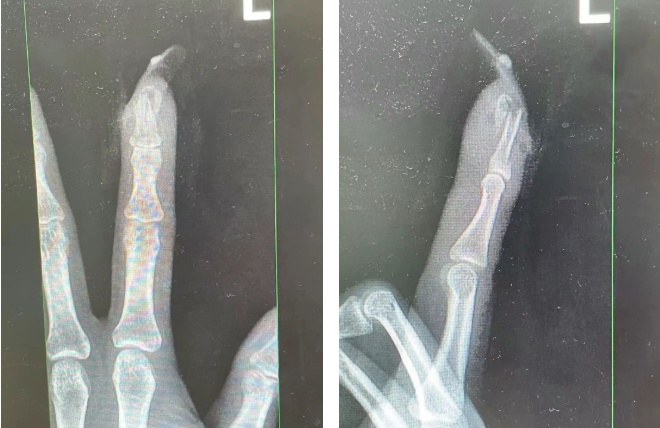

王女士受伤手指的X光影像。图源:杭州市临平区中西医结合医院

经检查

王女士指甲断裂

部分甲床外露

医生表示如果没有美甲

伤害不会这么严重

万幸经过手术

王女士恢复良好